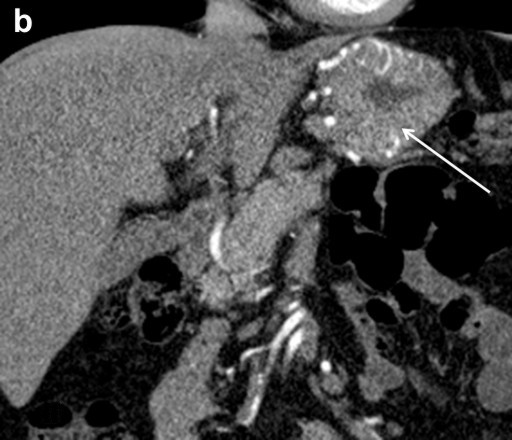

CT Angiography

Preceding surgery, the splenic artery was always seen on CT angiography as a thick stem with no other branches travelling to the spleen (Figures 7a and 8a). As a consequence of splenic artery resection, the whole or the bulk of its trunk were no longer available for evaluation by CT angiography after a spleen-preserving distal pancreatectomy with resection of the splenic vessels and, in all 10 cases, the gastroepiploic arcade was seen to have become the “highway” to the spleen within 7-30 days after surgery (Figures 7b, 8b, and 9). In two cases, due to technical reasons, 3D CT angiography was only carried out postoperatively but, in both cases, there were no doubts about the source of the blood supply to the spleen (Figure 9). In none of the 10 cases was any appreciable blood flow through the short gastric arteries visualized.

Thus, 3D CT angiography after a spleen-preserving distal pancreatectomy with resection of the splenic vessels did not reveal any reliable blood flow via the short gastric arteries. In all cases, the dominant role of the left gastroepiploic artery serving as the main blood supply to the spleen through the gastroepiploic arcade was observed.

Figure 8. Celiaco-mesenterial anatomy in а 59-year-old woman with a neuroendocrine tumor of the pancreatic body and tail. 3D CT angiography after the renal artery images were eliminated. a. Before surgery: the splenic artery thick trunk with no collaterals is shown. b. Ten days after a spleen-sparing distal pancreatectomy with resection of the splenic vessels: the spleen is fed through the gastroepiploic arcade. There are no other detectable major arteries to feed the spleen. c. After surgery, vertical view: the arrow is pointing to the gastroduodenal artery, i.e., the site of origin of the gastroepiploic arcade. GEA: gastroepiploic arcade; LGEA: left gastroepiploic artery; SA: splenic artery |